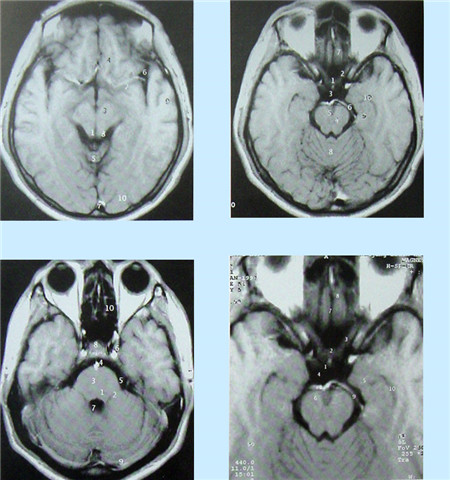

核磁共振血管成像(MRI)簡(jiǎn)介

核磁共振(MRI)又叫核磁共振成像技術(shù)。是繼CT后醫(yī)學(xué)影像學(xué)的又一重大進(jìn)步。自80年代應(yīng)用以來(lái),它以極快的速度得到發(fā)展。其基本原理是:將人體置于特殊的磁場(chǎng)中,用無(wú)線電射頻脈沖激發(fā)人體內(nèi)氫原子核,引起氫原子核共振,并吸收能量。在停止射頻脈沖后,氫原子核按特定頻率發(fā)出射電信號(hào),并將吸收的能量釋放出來(lái),被體外的接受器收錄,經(jīng)電子計(jì)算機(jī)處理獲得圖像,這就叫做核磁共振成像。

核磁共振成像無(wú)電離,對(duì)機(jī)體沒(méi)有不良影響。MRI對(duì)檢測(cè)腦內(nèi)血腫、腦外血腫、腦腫瘤、顱內(nèi)動(dòng)脈瘤、動(dòng)靜脈血管畸形、腦缺血、椎管內(nèi)腫瘤、脊髓空洞癥和脊髓積水等顱腦常見(jiàn)疾病很有效。

核磁共振成像設(shè)備價(jià)格昂貴,檢查費(fèi)用也較高,它與CT都可以提供斷層的靜態(tài)掃描圖像。

數(shù)字減影血管造影DSA腦血管圖像顯示 核磁共振MRI掃描腦組織圖像